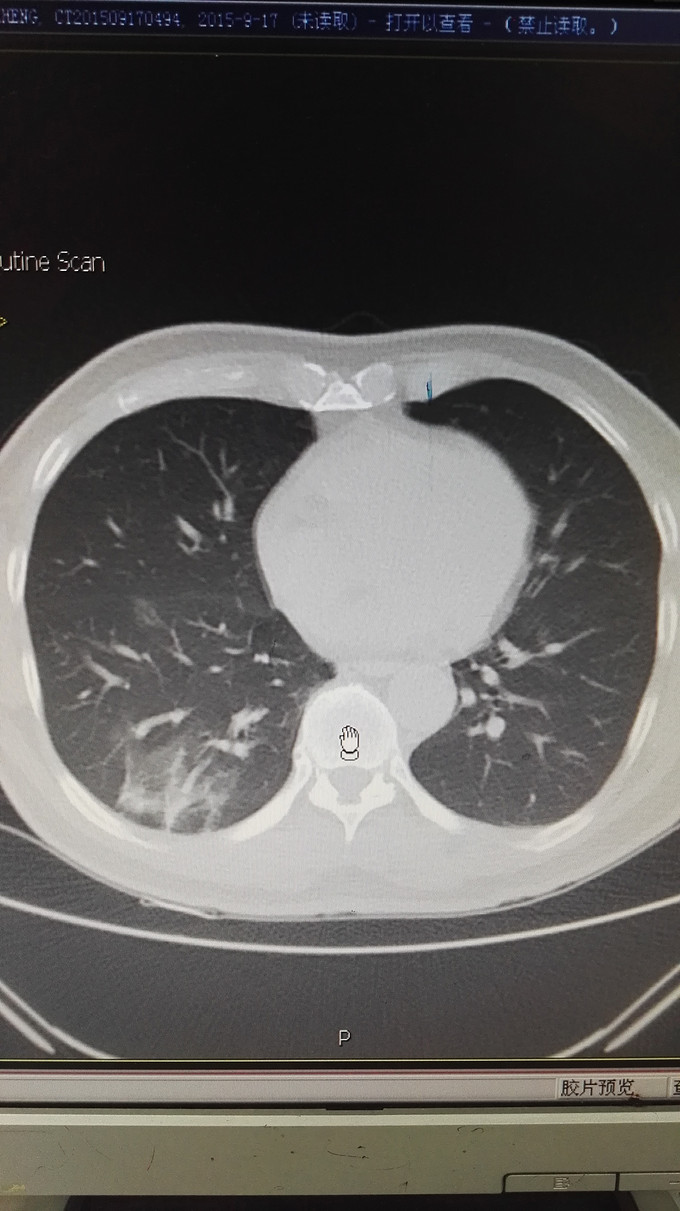

患者男,65岁,退休人员,因体检发现双肺阴影 半月入院。无不适症状。不嗜烟酒,有高血压、糖尿病史。

查体未见异常。 辅助检查:血常规、肿瘤指标、免疫指标、肝肾功能、痰涂片均未见异常。PCT、CRP不高。CT如图:右肺下叶多发斑片状影,左肺上叶蛇段、下叶少许条索状影,考虑双肺慢性炎症。

诊断:双肺阴影查因:肺炎? ; 高血压病 ;2型糖尿病 治疗,目前先进行抗感染及控制血压、血糖处理。